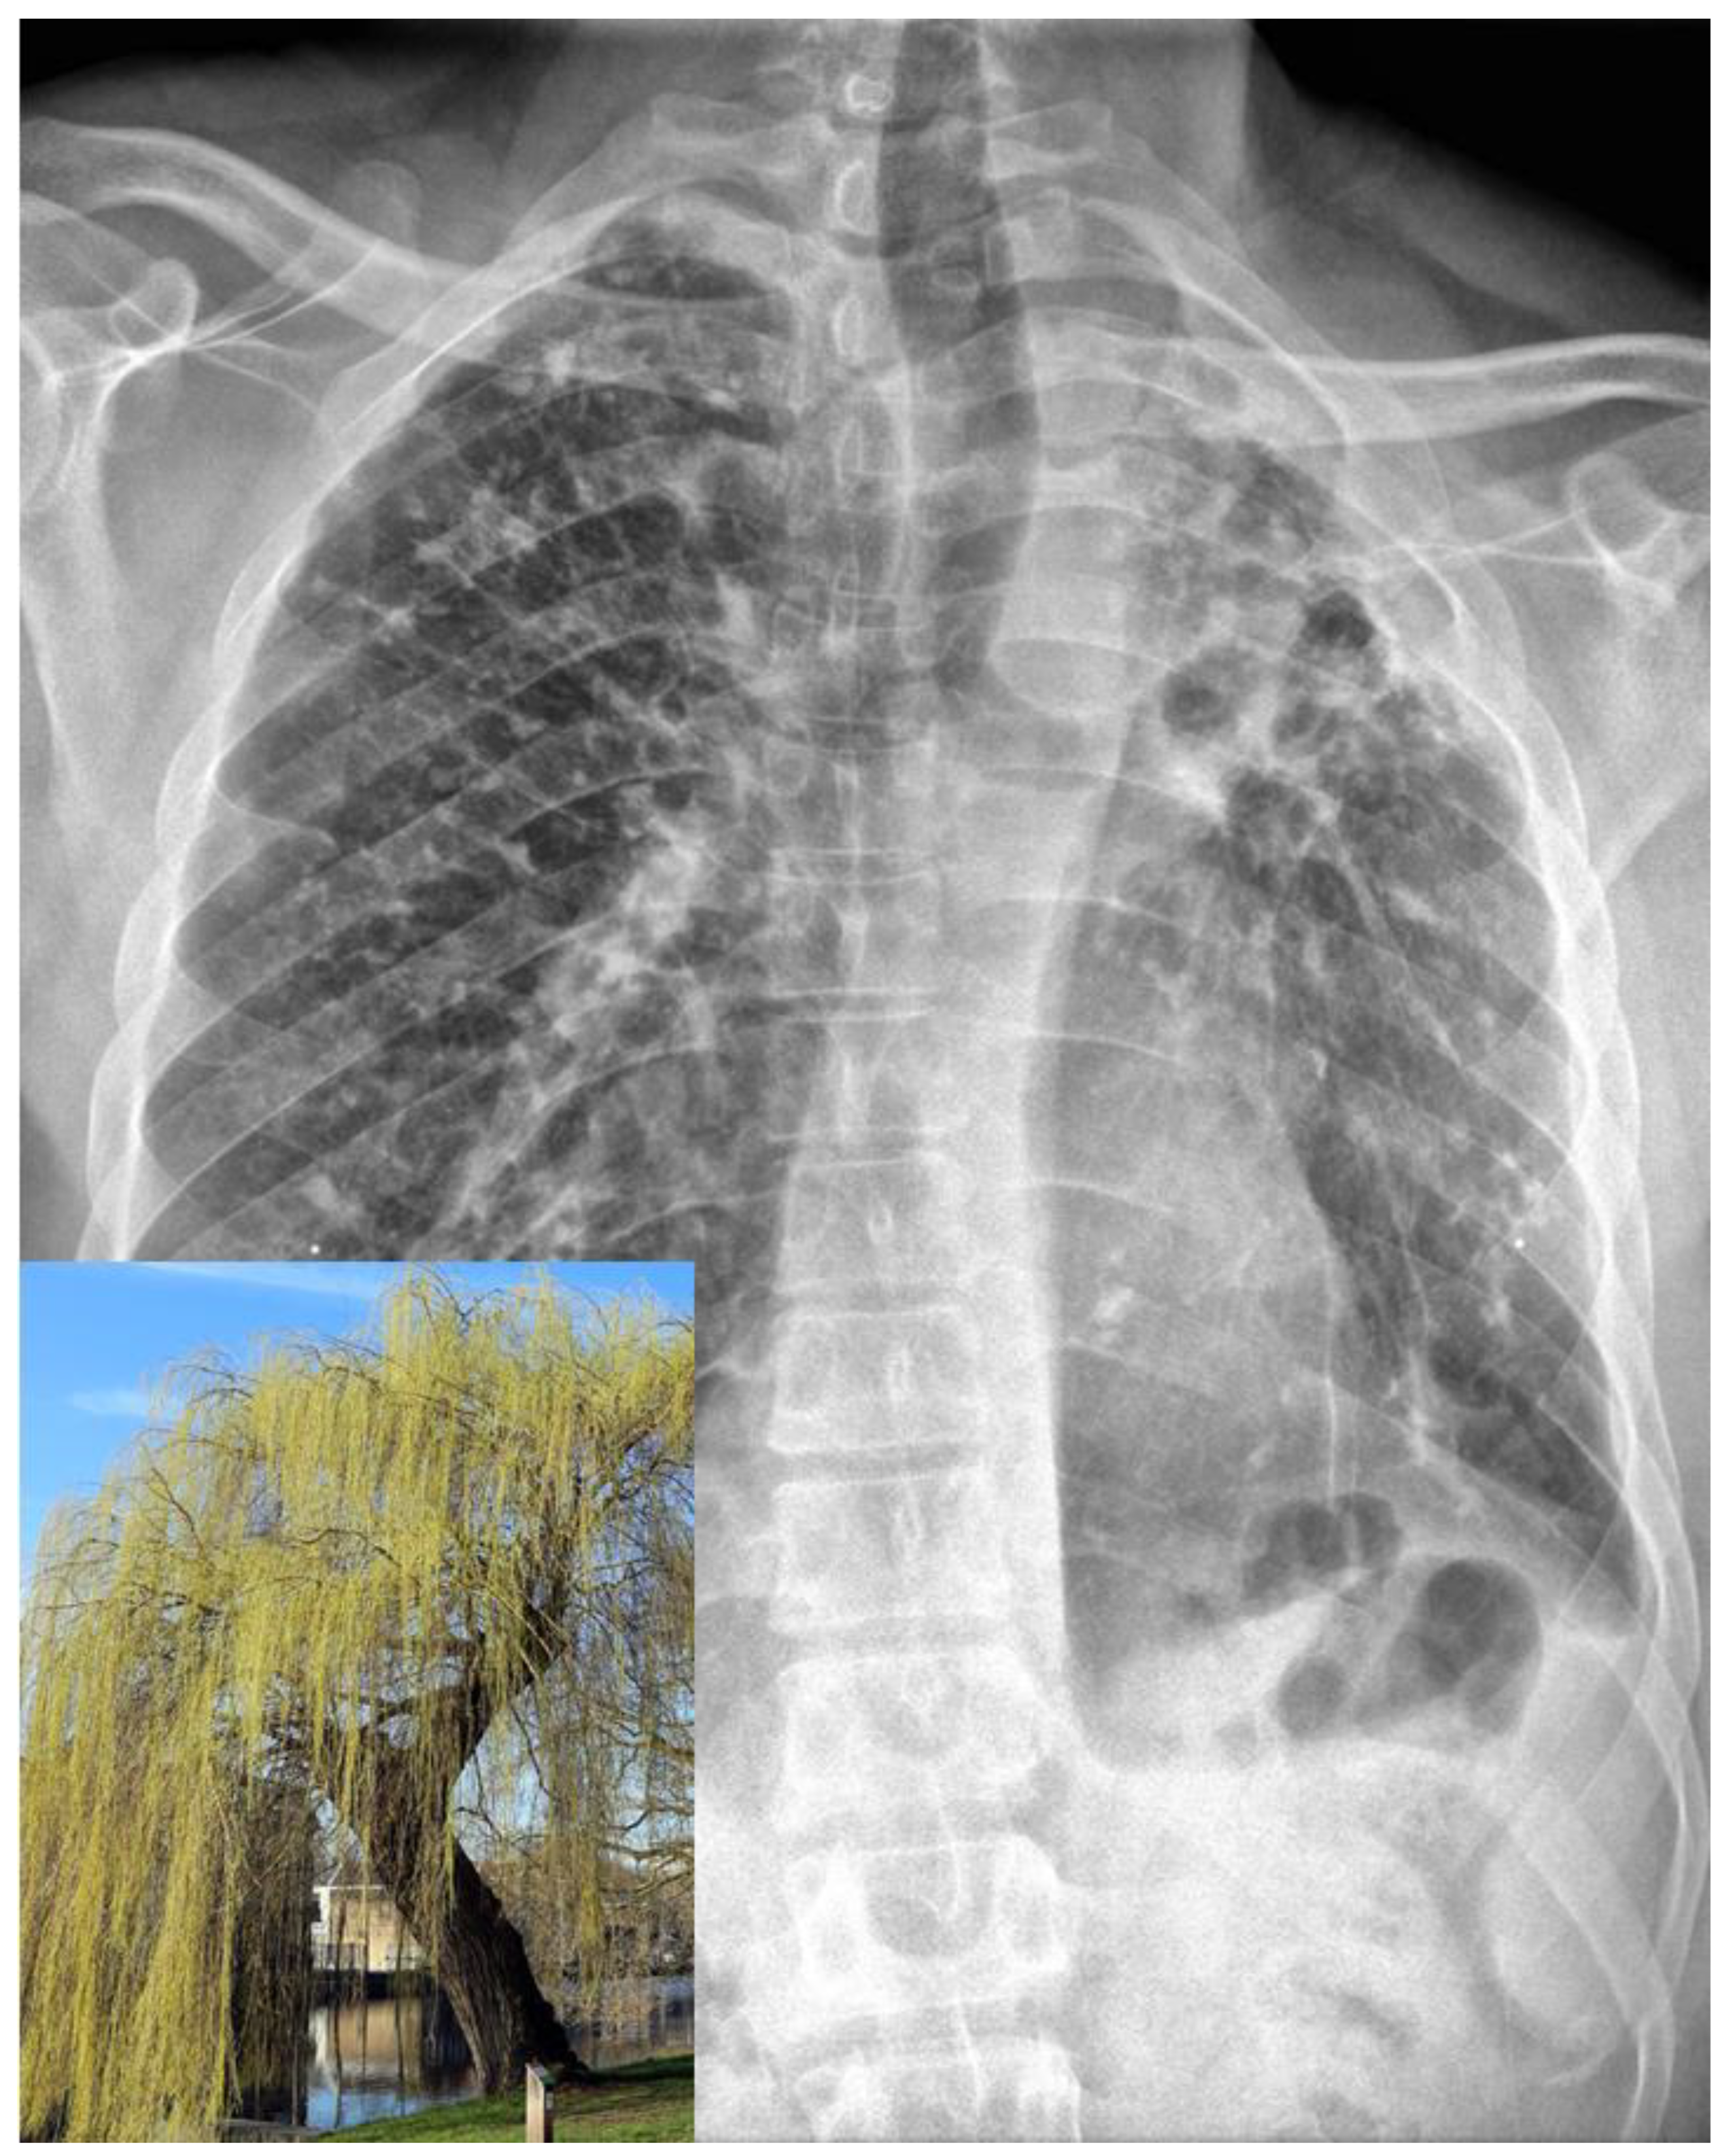

An initial workup revealed a normal blood count, metabolic panel, CPK and lactate, and a mildly elevated CRP (Table 1). A chest X-ray revealed bilateral calcified granulomata, along with significant volume loss and extensive scarring in the left upper lobe with retraction of the left hilum, summarized as the classic “weeping willow” pattern, consistent with his history of extensive tuberculosis (Figure 1), unchanged from a prior X-ray.

Figure 1.

The patient’s chest X-ray exhibits the classic “weeping willow” sign within the left hemithorax, which is a distinctive feature of pulmonary scarring induced by tuberculosis. This sign results from a combination of apical contraction, bronchial drooping, and fibrotic bands that extend down to the diaphragm, creating a resemblance to a weeping willow tree. Inlet, bottom left: weeping willow tree, for comparison. Inlet image courtesy of Sailko, CC BY 3.0, via Wikimedia Commons.

This case is also notable for the patient’s several prominent clinical findings consistent with postprimary tuberculosis. His physical exam was notable for amphoric breath sounds, breath sounds that are produced by the flow of air through a pulmonary cavity and are reminiscent of the sound produced by blowing air in a bottle with a wide opening (such as an ancient Greek amphora). Their presence is diagnostic of an underlying cavity [7,8], while their identification at the apex, such as in this patient, is highly suggestive of a disease that causes cavitary lesions in the upper lobes, such as tuberculosis. In addition, his chest X-ray showed the presence of the classic “weeping willow” sign, characteristic of tuberculosis-induced pulmonary scarring. It is the result of a combination of apical contraction, drooping of the bronchi, and fibrotic bands reaching down to the diaphragm, which resembles the weeping willow tree [9] (Figure 1).